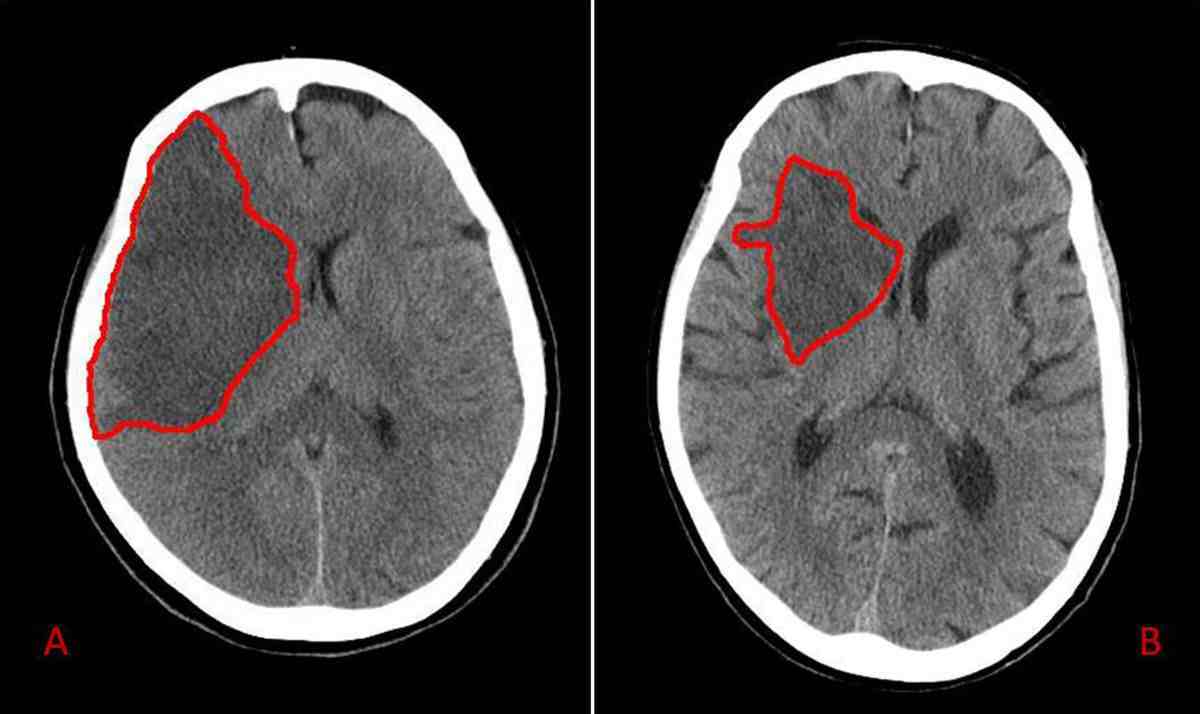

Outline the artery & pathology involved in A & B

MCA Ischaemia

A - total ischaemia

B - partial ischaemia